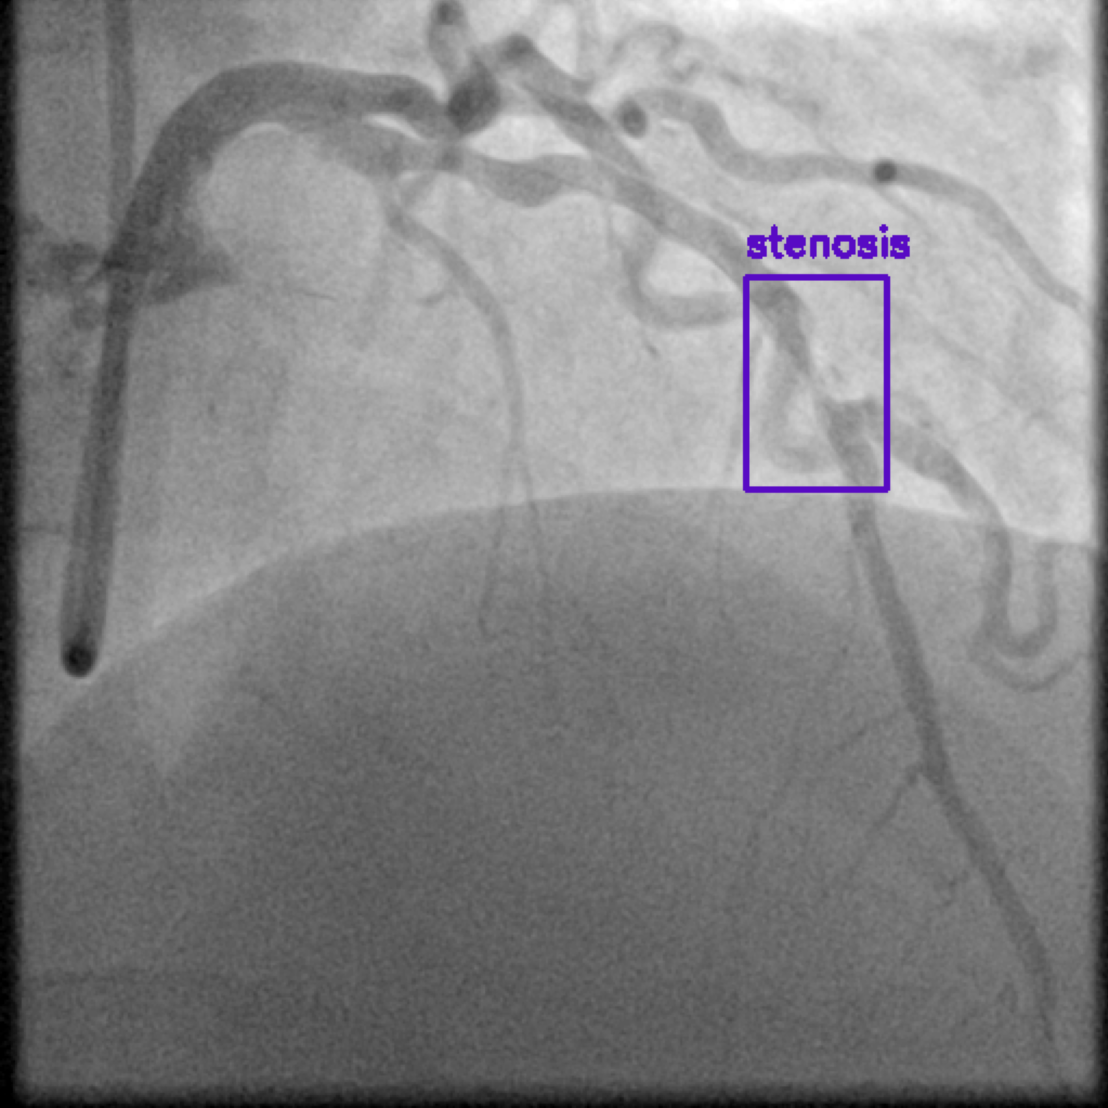

图1 X 射线冠状动脉造影图像,紫色高亮区域显示狭窄。狭窄表示血管变窄,限制了流向心肌的血流。

冠状动脉疾病主要发生在供应心脏的主要血管受损或者发生疾病时,通常由动脉中斑块堆积引起。这会导致血管变窄(狭窄),从而限制流向心肌的血流。若不及时治疗,可能会导致心绞痛(胸痛)、心脏病发作,甚至死亡。